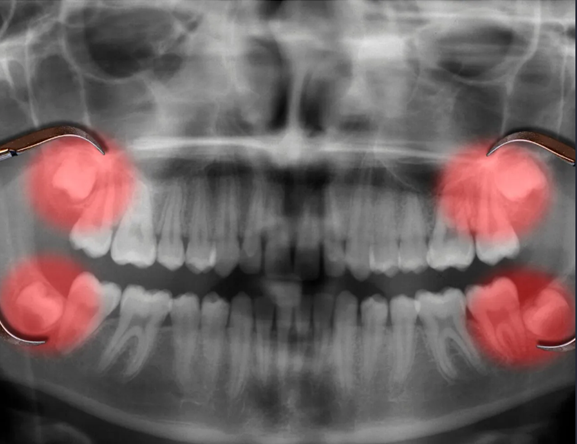

Morfología dentaria y oclusión es una de las materias básicas de primer semestre de la carrera de odontología, cuya importancia radica en impartir información básica sobre las características anatómicas y fisiológicas de cada diente y su relación con el sistema estomatognático; además los factores determinantes de los movimientos mandibulares y su relación con la morfología oclusal, conjugando la armonía y estabilidad de los componentes individuales del sistema masticatorio. Constituye todo lo antes mencionado la mayor parte de las maniobras que realiza el odontólogo, fundamentales para llegar a un diagnostico adecuado y tratamiento correcto de las disfunciones mandibulares, también restaurando día a día la morfología dentaria de los pacientes.